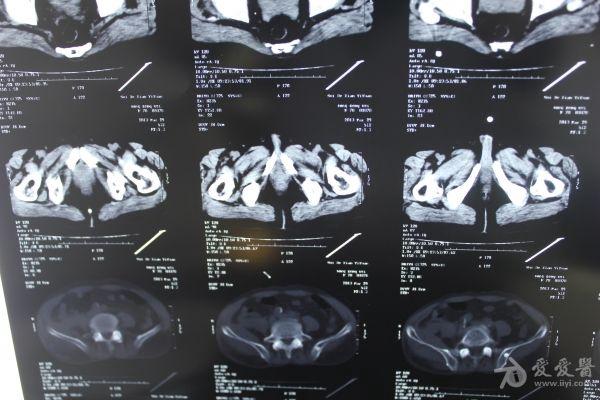

老年患者78岁,反复腰背部溃烂流脓4年,既往30年前曾在包块处排出蛔虫一条。CT:

明日手术探查